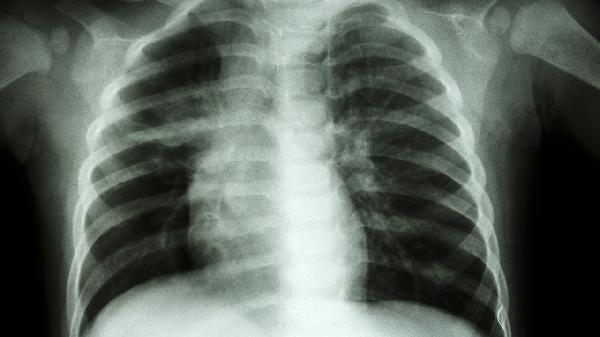

使用矽肺宁片过程中需要避免接触粉尘,做好呼吸道防护工作。建议患者戒烟限酒,保持居住环境空气流通,适当进行呼吸功能锻炼。矽肺病患者需定期复查胸片及肺功能指标,在日常生活中应注意预防呼吸道感染,天气变化时及时增添衣物。饮食上应多摄入优质蛋白及富含维生素的食物,保持营养均衡。如出现发热、呼吸困难加重等情况应及时就医。